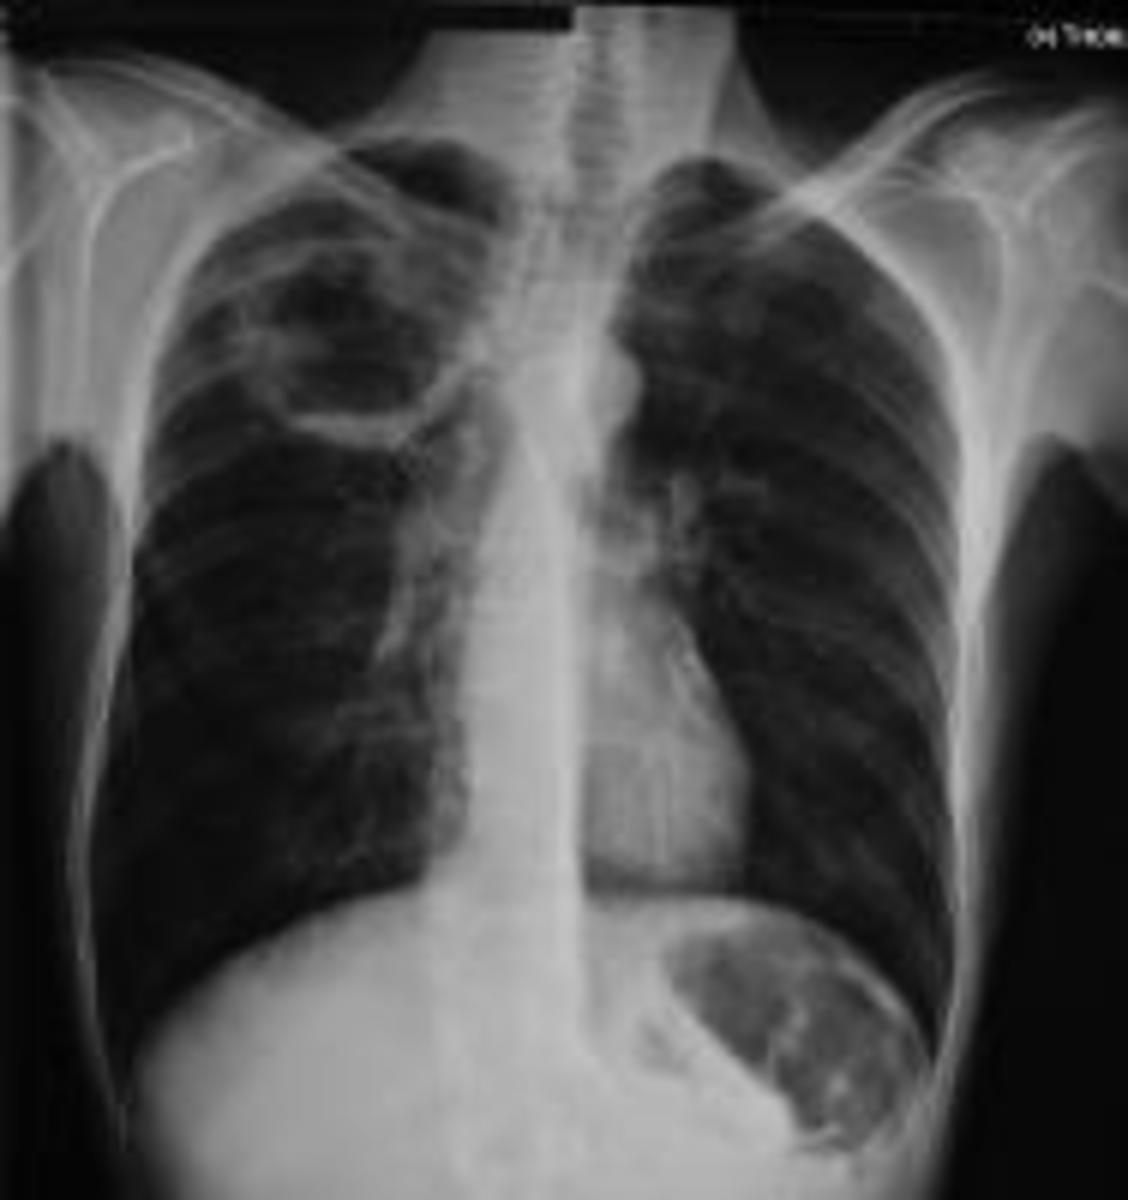

Lung abscesses, Xray Stock Image F039/3323 Science Photo Library

lung abscess film chest xray PA upright show left lung abscess 2460065 Lung Abscess X Ray Findings Distinguishing between an empyema and an abscess. lung abscess is a type of liquefactive necrosis of the lung tissue. a lung abscess is characterized as a localized collection of pus or necrotic tissue within the lung parenchyma,. a lung abscess is circumscribed, purulent infection contained within the lung parenchyma. It is most commonly caused by aspiration. Visual. Lung Abscess X Ray Findings.